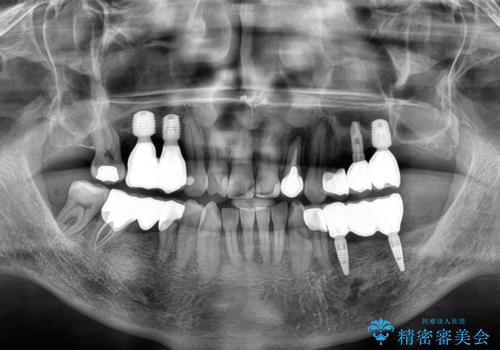

欠損の多い奥歯 インプラントによる補綴治療

上顎は左右ともに骨が少ない状態であり、特殊なドリルを用いた歯槽骨の拡大や自家骨挙上などを行いながらインプラントを埋入していくこととしました。

地元に戻られる前に無事に治療を終えることができました。

今後は東京出張のタイミングでメインテナンスに通院していただきながら、インプラントの状態をチェックしていくことになります。